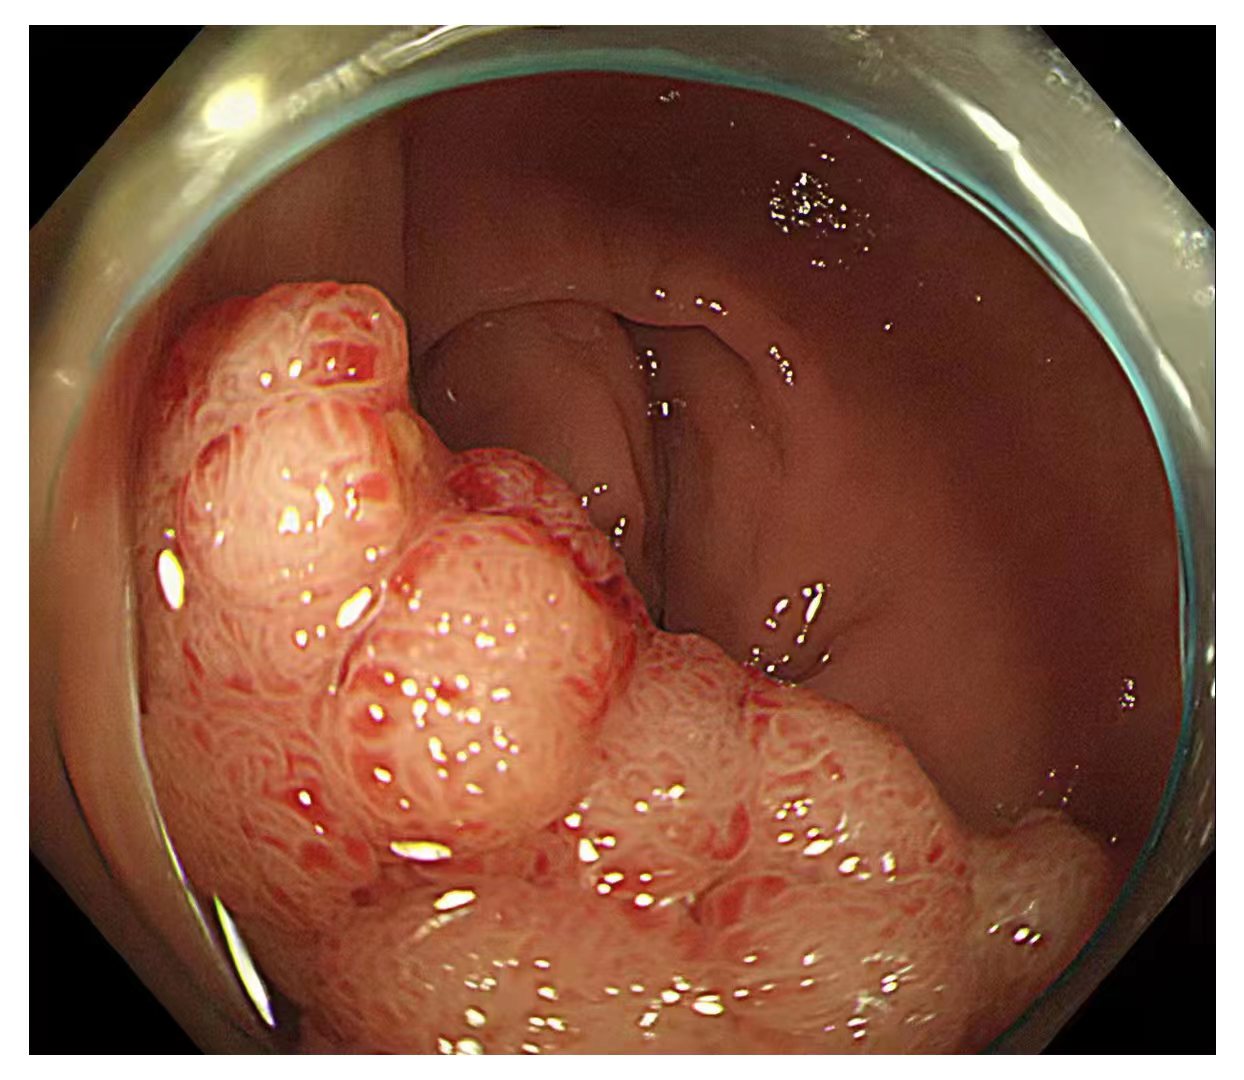

内镜中心在胃镜检查、结肠镜检查、息肉治疗、取除异物、超声内镜检查和食管支架术、内镜下黏膜剥离术等方面开展了大量的工作,结肠的回肠末端到达率98%,结肠息肉检出率达35%,早癌检出率1.5%。

内镜中心独立完成了多例食管、胃、结肠早癌完整切除术,并成功开展了食管良性狭窄切开术,间质瘤挖除术,食管癌伴食管狭窄支架置入术,消化道异物取出术,痔疮Ⅱ度以内的硬化术等。